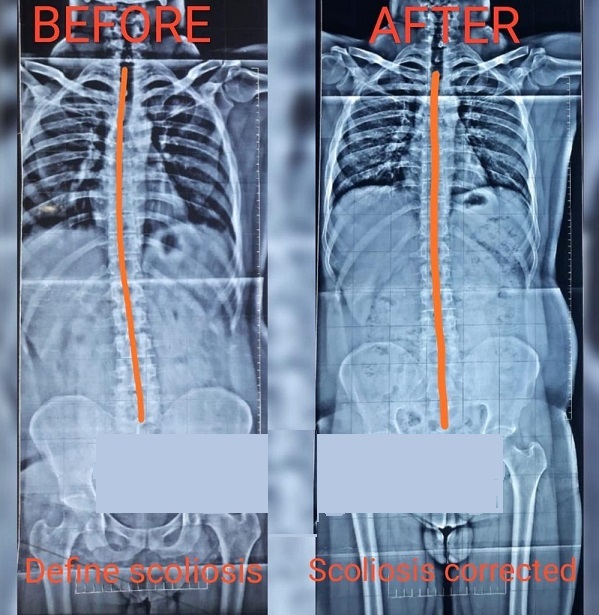

Scoliosis

2: Scoliosis